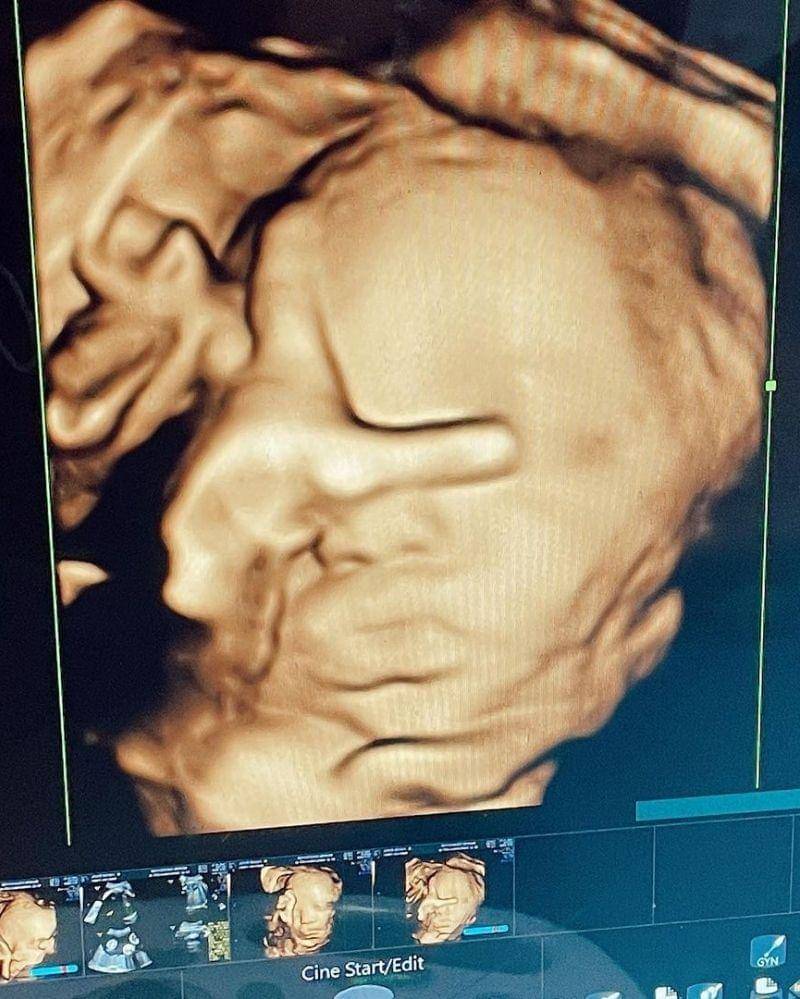

18. Khan Gionino, putra Meiza Aulia Coritha dan Eza Gionino

Selanjutnya ada foto USG kehamilan Meiza Aulia Coritha, istri dari pesinetron Eza Gionino. Saat itu Meiza sedang mengandung putra keduanya yang kini diberi nama Khan Gionino.

Pada 21 Februari lalu, Meiza akhirnya melahirkan putra keduanya tersebut dan kini telah berusia 1 tahun. Tak lama lagi Khan juga akan menjadi seorang kakak lho, Ma.